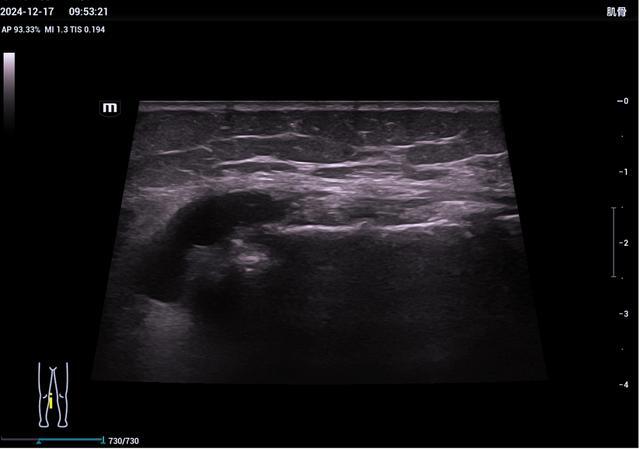

▲膝内侧副韧带损伤性囊肿

▲距腓前韧带断裂

(III°损伤)